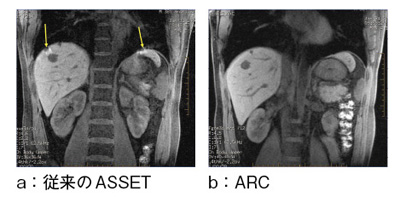

20220914082754.jpg。放射線科|八潮中央総合病院。正常画像と並べてわかる腹部・骨盤部MRI―ここが読影のポイント。対象検査部位・撮像手法|UNB住吉神社前クリニック 放射線科。「腹部のMRI」荒木 力定価: ¥ 13000#荒木力 #荒木_力 #本